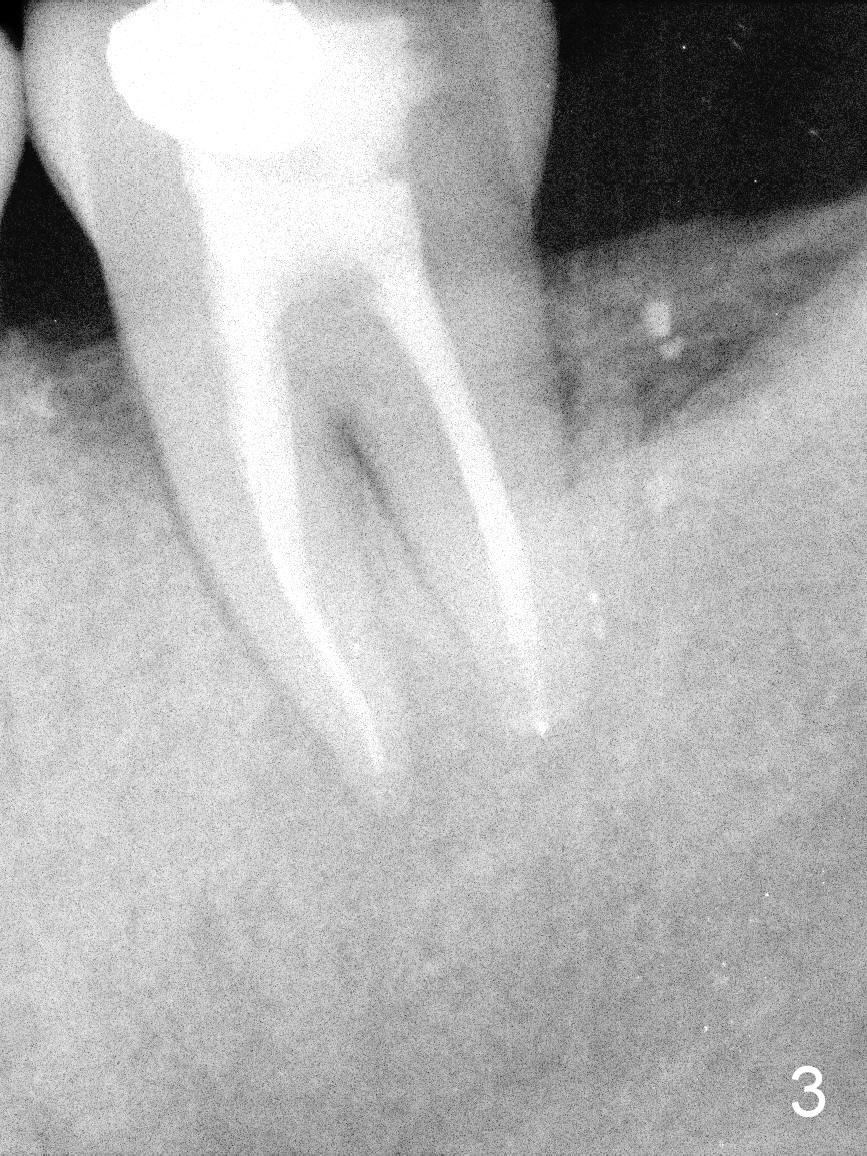

A 55-year-old man must be a dental phobic. With a fistula (Fig.1 <) and large radiolucency associated with the lower left 2nd molar, he postponed root canal therapy for 2 years and 8 months (Fig.2). Later he refused to have crown for the tooth. Three years and 5 months later, the radiolucency seems to have been resolved (Fig.3), but the tooth has fractured with buccal infection. The patient is unwilling to accept treatment of extraction (no antibiotic socket treatment) and immediate implant (Fig.4).